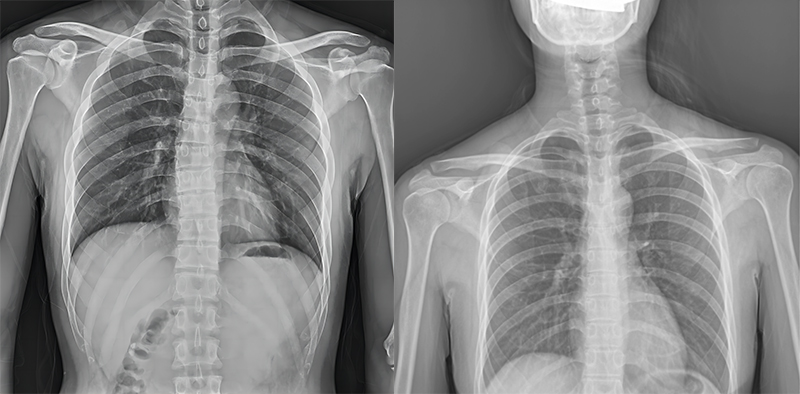

百微米DR與普通像素尺寸DR的影像對比

以胸部攝影為例,通過對比百微米大平板與普通像素尺寸平板的影像,可以看到百微米影像對比度適中,圖像清晰度更高,成像細節更加豐富。在胸部影像顯示中肺門影結構、肺紋理等細節展示更清楚,兩側膈肌邊緣、心臟、縱隔邊緣清晰銳利顯示,在影像中都可以清晰地顯示胸部細微結構,滿足臨床診斷要求。